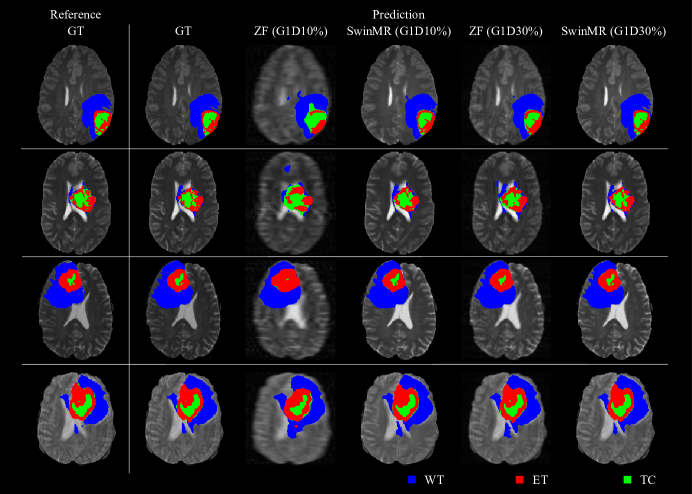

Table 4 shows the result of SwinMR trained with BraTS17 FLAIR, T1, T1CE and T2 respectively. Figure 18 displays the samples of the reconstruction of different modalities. Table 5 and Table 6 show the IoU and Dice score of the segmentation task. Figure 19 displays the sample of the segmentation task.

According to Table 5 and Table 6, the IoU and Dice score of reconstructed MR images are improved compared with ZF MR images and much closer to the score of GT MR images. According to the Mann-Whitney Test, the IoU and Dice score distributions of the reconstructed MR images using the Gaussian 1D 30% mask are not significantly different from the distributions of the GT MR images (p>0.05𝑝0.05p>0.05).

Refer to caption

Figure 19: Samples of segmentation results for SwinMR on the BraTS17 dataset. Col 1: Segmentation reference; Col 2: Segmentation prediction using GT images; Col 3: Segmentation prediction using zero-filled MR images (ZF) undersampled by Gaussian 1D 10% mask (G1D10%); Col 4: Segmentation prediction using reconstructed MR images undersampled by G1D10%; Col 5: Segmentation prediction using ZF undersampled by Gaussian 1D 30% mask (G1D30%); Col 6: Segmentation prediction using reconstructed MR images undersampled by G1D30%. Blue area: Whole tumour (WT); Red area: Enhancing tumour (ET); Green area: Tumour core (TC).